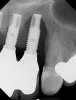

Several factors increasing the risk of peri-implantitis have been reported. Lack of access to the intaglio surface of the implant-supported prosthetics and poor oral hygiene of the implant is reported to increase the risk of peri-implantitis (Figure 3 through Figure 5). Concave intaglio design prevents oral hygiene access (Figure 6). Monje reported that 77.2% of the peri-implantitis cases had inadequate access for cleansability. 9 Serino and Ström found that 74% of the implants had no access to proper plaque control and highlighted the role of prosthesis design.10 Katafuchi suggested that a shallow emergence angle (EA) with a straight or concave transmucosal profile at the interproximal sites should be considered to minimize peri-implantitis risk for bone-level implant.11

(3.) Prosthesis without access to the intaglio interface.

Figure 3

(4.) Intagilo inflammation of the soft tissue following removal of the prosthesis.

Figure 4

(5.) Prosthesis intaglio surface.

Figure 5